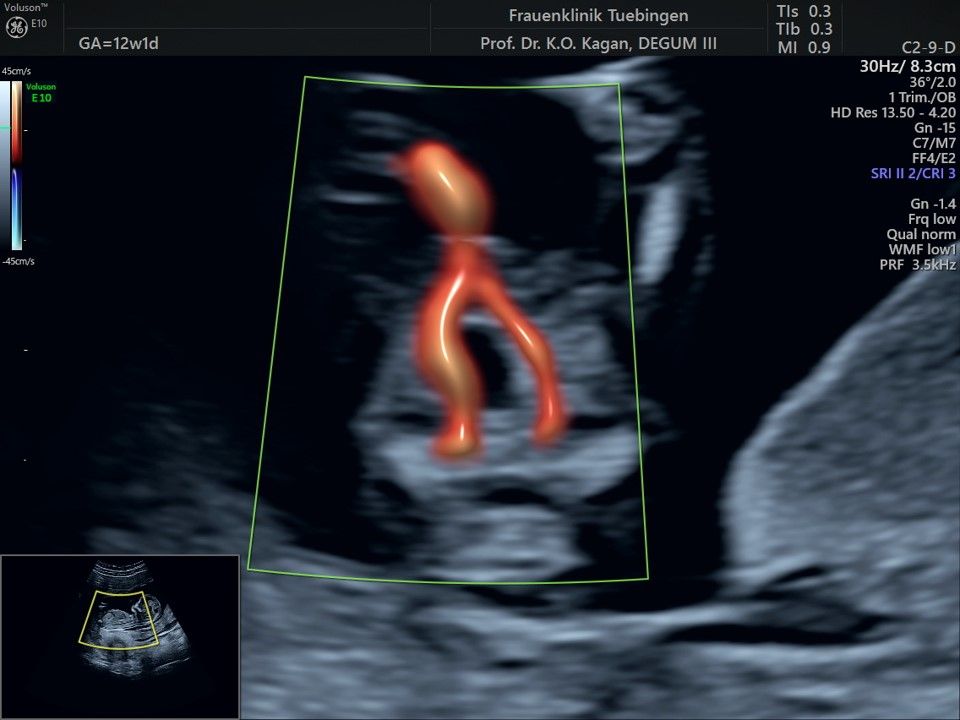

Das Ergebnis der Ultraschalluntersuchung ist wegweisend. Dabei wird der Fet vermessen, die Organe werden untersucht und die sonographischen Marker zur Risikoberechnung für Chromosomenstörungen werden beurteilt. Das sind: die Nackentransparenzdicke, Nasenbein sowie der Blutfluss in der rechten Herzhälfte und im Ductus venosus, einem Gefäß in der Leber des Feten.